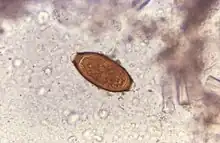

The disease usually spreads when people eat food or drink water containing these worms' eggs.[1] This may occur when contaminated vegetables are not fully cleaned or cooked.[1] Often these eggs are in the soil in areas where people defecate outside and where untreated human feces is used as fertilizer.[2] These eggs originate from the feces of infected people.[1] Young children playing in such soil and putting their hands in their mouths also become infected easily.[1] The worms live in the large bowel and are about four centimetres in length.[2] Whipworm is diagnosed by seeing the eggs when examining the stool with a microscope.[3] Eggs are barrel-shaped.[8] Trichuriasis belongs to the group of soil-transmitted helminthiases.[9]

Adult worms are usually 3–5 centimetres (1.2–2.0 in) long, with females being larger than males as is typical of nematodes. The thin, clear majority of the body (the anterior, whip-like end) is the esophagus, and it is the end that the worm threads into the mucosa of the colon. The widened, pinkish-gray region of the body is the posterior, and it is the end that contains the parasite's intestines and reproductive organs. T. trichiura eggs are prolate spheroids, the shape of the balls used in Rugby and Gridiron football. They are about 50–54 μm (0.0020–0.0021 in) long and have polar plugs (also known as refractile prominences) at each end.

A stool ova and parasites exam reveals the presence of typical whipworm eggs. Typically, the Kato-Katz thick-smear technique is used for identification of the Trichuris trichiura eggs in the stool sample. Trichuria eggs often appear larger and more swollen on Kato-Katz preparation compared to when using other techniques.[18]

Trichuriasis can be diagnosed when T. trichiura eggs are detected in stool examination. Eggs will appear barrel-shaped and unembryonated, having bipolar plugs and a smooth shell.[20] Rectal prolapse can be diagnosed easily using defecating proctogram and is one of many methods for imaging the parasitic infection. Sigmoidoscopies show characteristic white bodies of adult worms hanging from inflamed mucosa ("coconut cake rectum").[21]